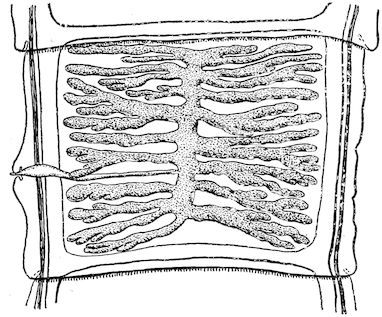

Fig. 3.—Pig suffering from osseous cachexia (fourth stage).

Such shocks would be of no importance to a healthy animal, but to one suffering from osseous cachexia, any violence, or even the slightest muscular effort may be followed by fracture of the gravest character, involving even the vertebral column. In cows the pelvis, femur, and tibia are most frequently injured.

In horses, particularly in riding horses, fractures are commonest in the region of the forearm, cannon bone, and anterior phalanges. So extremely fragile are the bones at this stage that the horse represented herewith broke twelve ribs at one time by simply falling on its side. It is interesting to note that such fractures are never accompanied by any extensive bleeding. They have little tendency to repair, no real callus formation occurs, and on post-mortem examination one often finds the ends unconnected by temporary callus, worn, and rounded by reciprocal friction.

At this stage but under other circumstances, the animals show great reluctance to rise, remaining down for twelve to twenty-four hours without shifting their position. If forced to get up, they stand as though fixed in one position, the respiration and circulation become rapid, and they soon grow tired and fall.

114. The fourth phase, or period of osteomalacia, i.e. softening of the bones, is also the last. It is rarely seen in large animals like horses and oxen, because accidents so often accompany the preceding stages and necessitate slaughter; but it is common in goats and pigs.

In this phase the bones become elastic, soft and depressible, yielding to the pressure of the operator’s fingers.

Fig. 4.—Deformity of the face in the horse shown in Fig. 2.

The flat bones are particularly liable to this change, which is common to domesticated animals. The bones of the head are the first to suffer; later those of the pelvis. The lower jaw becomes swollen, particularly about the centre of the branches which may attain three, four, or five times, their normal thickness.

The depression in the submaxillary space disappears. The upper jaw undergoes similar changes, becoming deformed and thickened until the cavities of the sinuses and the hollow appearance of the palate are lost, while the face is so changed that it cannot be recognised as that of a horse, goat, etc.

The molar teeth are almost buried, their tables alone being visible at the bottom of a depression, the edges of which rise above the neighbouring parts (pig).

Mastication is clearly impossible, the jaws appear paralysed, the muscles powerless, and only swallowing is possible, a fact which explains why life is only prolonged to this stage in animals which can be fed with a spoon or bottle (pigs and goats). The bones of the cranium, although greatly changed in texture, are always less deformed than those of the face.

The changes are such that it is often easy with a mere post-mortem knife to cut the head completely in two. Osseous tissue, properly so-called, has disappeared.

All the constituent tissues, with the exception of the skin and muscles, i.e., the bone, periosteum and aponeuroses, have the appearance and consistence on section of the fibro-lardaceous tissue seen in chronic inflammation.